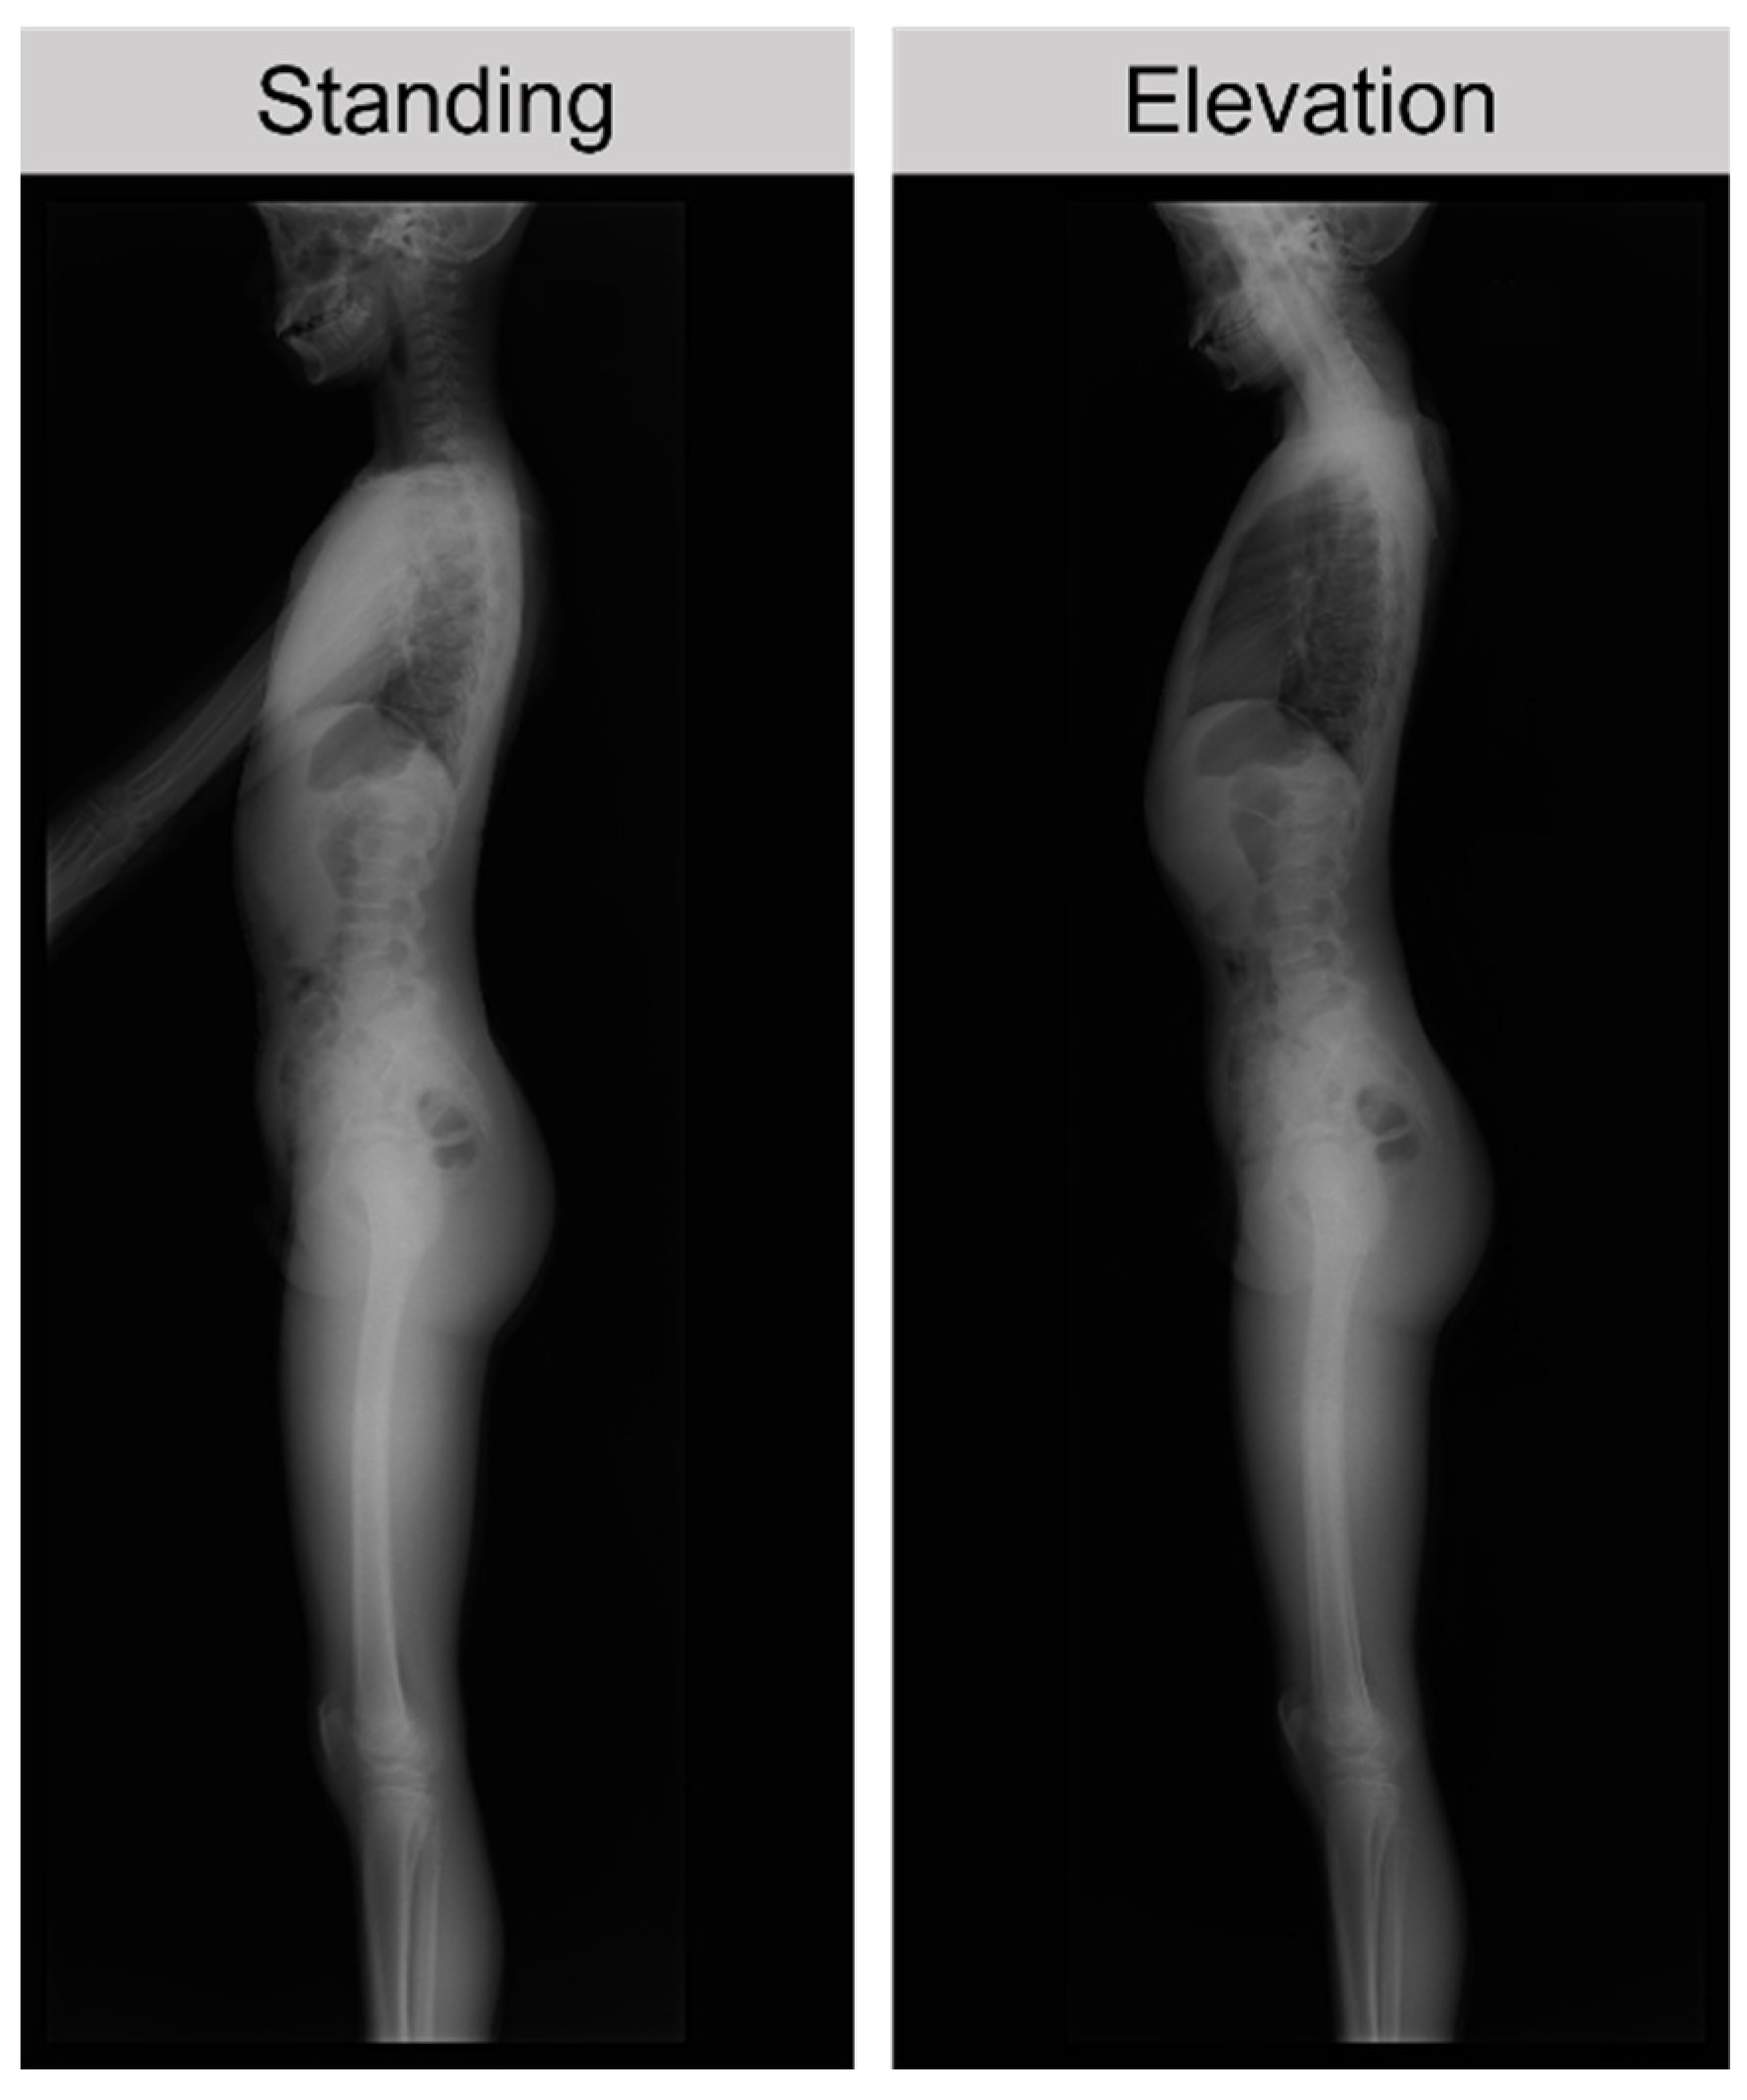

X-ray films were taken in the standing position and with upper limb elevation (elevation position) (Figure 1). During elevation, the patient was instructed to elevate both upper limbs to the maximum. The LL and SS were measured using two types of X-ray films. TK was measured using standing X-ray films.

Figure 1.

Patient position for X-ray evaluation. The patient was instructed to elevate both upper limbs to the maximum during elevation.